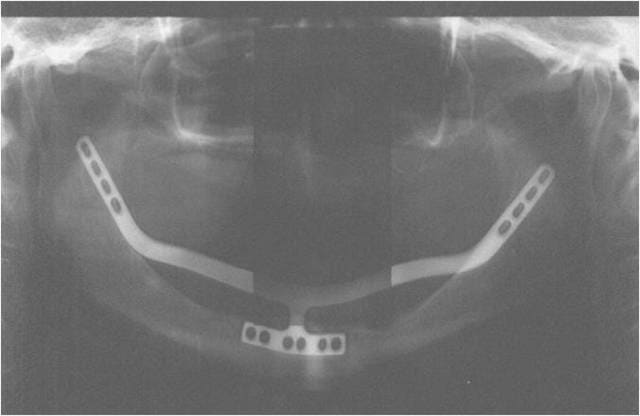

1. Les plaques sont en titane

2. oui on les les plie pour les adapter à la courbure du trigone rétromolaire, du zygoma et de la zone canine dépourvue de bosse qd très résorbée

3. Une partie ou le tout peut être posé de façon endostée mais également totalement sous périostée avec un biomat qui en s ossifiant va l englober

Celle ci a étté posée par voie linguale et de façon totalement endostée ( 6 ans de recul )

Le blocage primaire est assuré par les vis d ostéosynthèse